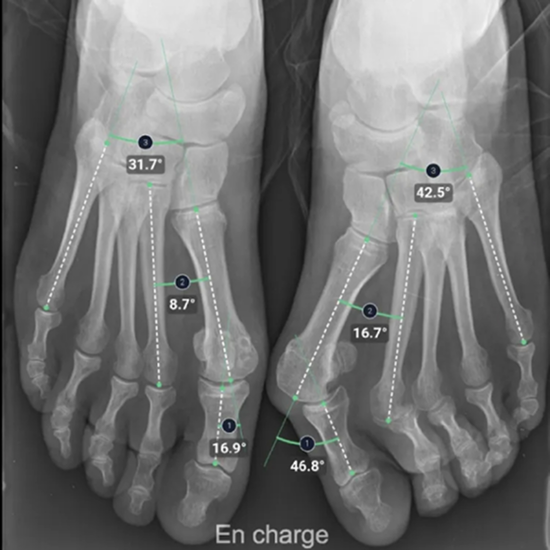

BoneMetrics: Automation of MSK Measurements and Workflow Optimization

With the aid of BoneMetrics, the capture of MSK measurements can be automated. Moreover, workflow optimization can be achieved through unparalleled precision in X-ray and EOS acquisitions.

BoneMetrics automatically performs standard measurements for the feet, legs, pelvis/hips, and spine.

Through accurate point placement and easily understandable displays, the introduction of the software allows you to direct your attention to more critical tasks.

By introducing AI-supported standardization, variability can be reduced and reproducibility can be ensured.

Clinical studies prove that BoneMetrics matches the expertise of MSK radiologists, enabling your practice to provide the best possible service to patients.